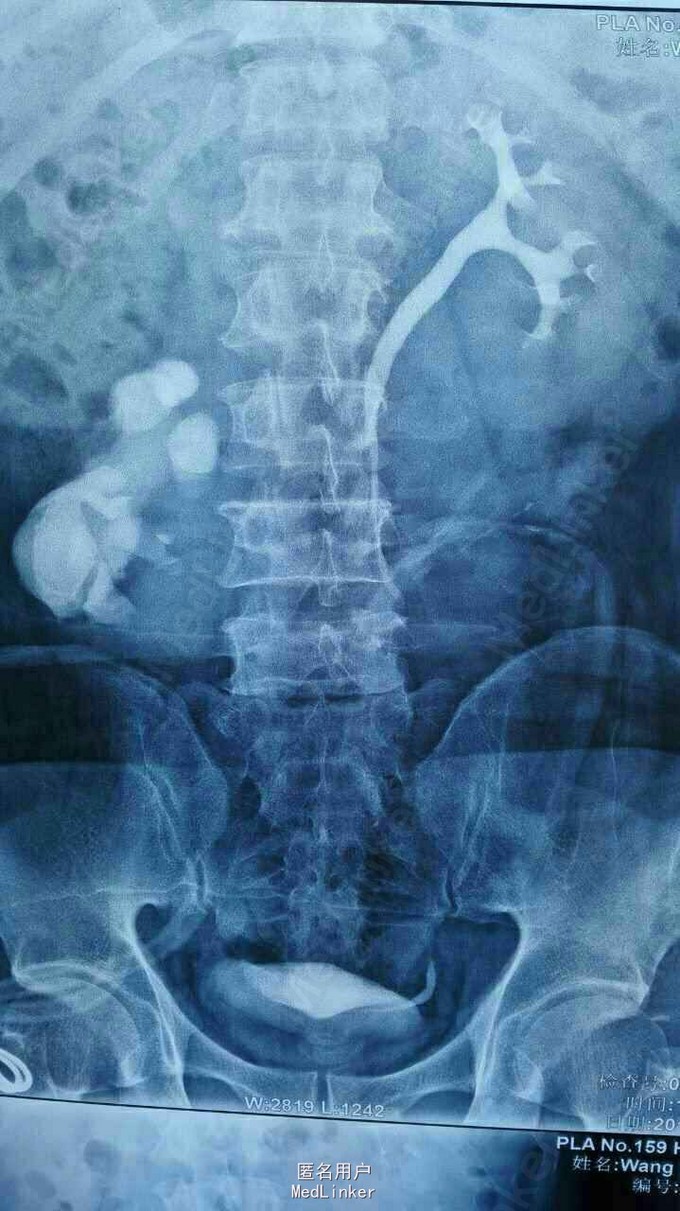

异位肾结石

诊断:右侧异位肾结石并肾积水。 拟行经皮肾镜碎石取石术,但因庙小,患者要求上级医院治疗。

请问各位如遇到这样患者如何治疗,是切肾还是取石?